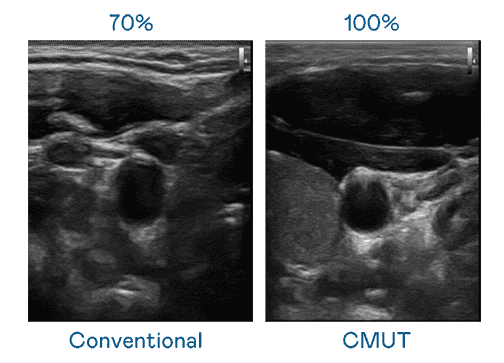

CMUT 技术是一种用电容式微机电元件来产生超音波讯号的技术。。与传统 PZT 压电式技术相比,,,CMUT 频宽增加 30%,,,更宽频的超音波讯号让影像解析度大幅提升,,,,是实现高影像品质医疗超音波扫描、、促进精准医疗发展的关键技术。。。。

大频宽带来超清晰影像

超音波影像的解析度高低,,,,首先取决于探头能发出的讯号频宽。。人生就是博 CMUT 可提供高清晰的超音波讯号,,提供高频宽、、、、高灵敏度、、、、影像纹理细节更高的超音波影像,,协助医护人员缩短影像判读时间及利用精准的医疗影像进行诊断。。。。